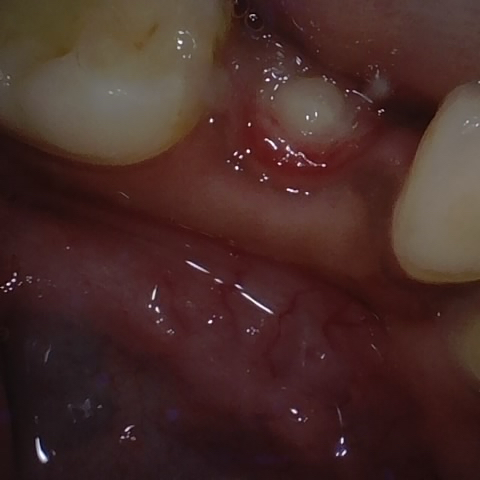

Annotated as "Good"